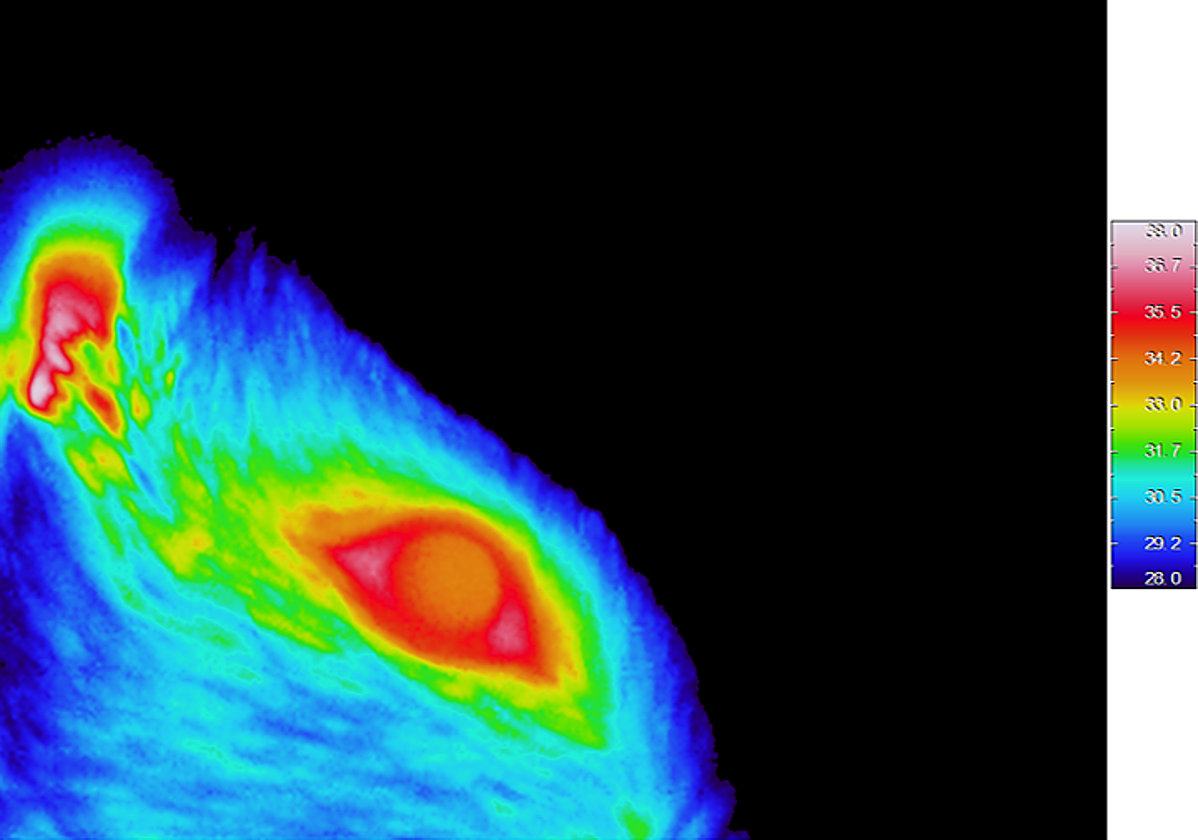

Imagen de termografía por infrarrojo en una rata despierta. TA